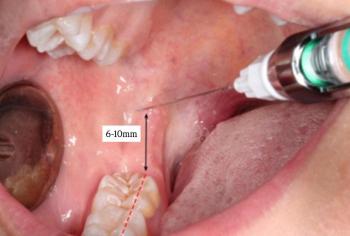

- Impaction / Impacted Tooth Extraction The best way is always select the advanced and experienced dentist for impacted tooth extraction is crucial, especially in Cebu, Philippines, where the procedure can present unique challenges. 9 things to remember during Impaction and Impacted Tooth Extraction